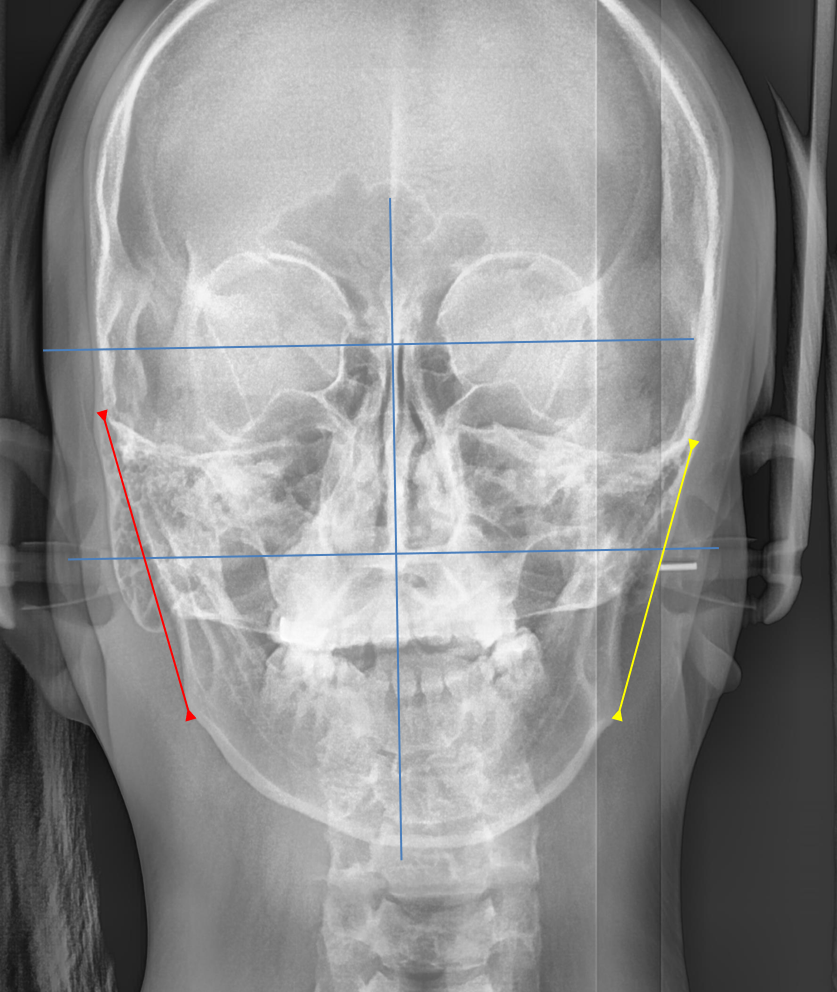

턱이 작으면 위아래 치아가 안정적으로 맞물리기 어렵습니다. 특정 부위가 먼저 닿거나 한쪽이 더 높게 물리면서 교합 높이의 불균형이 생기는데, 이것이 겉으로 보이는 비대칭을 더욱 도드라지게 만듭니다. 사실 이 환자분은 골격적으로 우측 뼈가 더 긴 상태이기도 하셨는데요. 잘못된 교합이 이러한 선천적 비대칭을 더욱 심화시키고 있었던 것입니다.

오른쪽(빨강)턱의 길이가 왼쪽(노랑)보다 길다. 뼈의 길이는 수술로만 바꿀 수 있다.